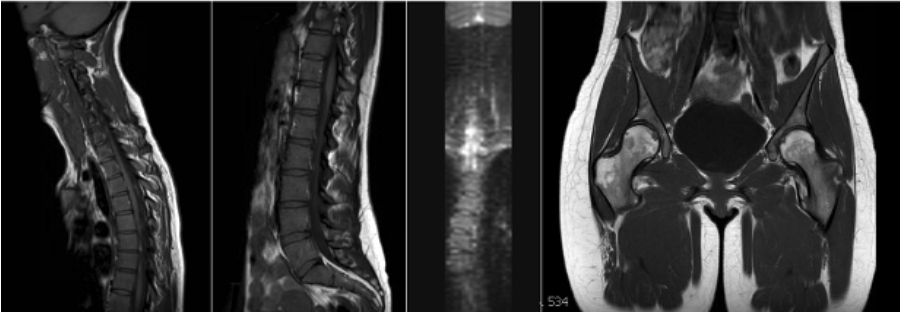

| Sequence | Weighting | Change Parameters? | Change # slices? | Coverage/ Angulation | Notes |

|---|---|---|---|---|---|

| SAG (Upper Spine) | T1 | NO | NO | Cover C2-T10 | |

| SAG (Upper Spine) | T2 STIR | NO | NO | Same as SAG T1 (Upper Spine) | |

| SAG (Upper Spine) | DWI | NO | NO | Same as SAG T1 (Upper Spine) | MPR in Coronal Plane.2.5 skip 0 |

| COR MPR | MPR | - | - | Reformat 2.5 skip 0 | Reformatted from SAG DWI |

| SAG (Lower Spine) | T1 | NO | NO | Cover T8-S5 | |

| SAG (Lower Spine) | T2 STIR | NO | NO | Same as SAG T1 (Lower Spine) | |

| SAG (Lower Spine) | DWI | NO | NO | Same as SAG T1 (Lower Spine) | MPR in Coronal Plane.2.5 skip 0 |

| PELVIS3 plane SURVEY | SURVEY | - | - | Include hip joints | |

| COR PELVIS | T1 | NO | NO | Center the FOV with the middle point in the region of L5-S1 . NO ANGLE. | Cover entire pelvis. |

| COR PELVIS | T2 STIR | NO | NO | Same as COR PELVIS T1. NO ANGLE. | |

| COR PELVIS | DWI | NO | NO | Same as COR PELVIS T1. NO ANGLE. |